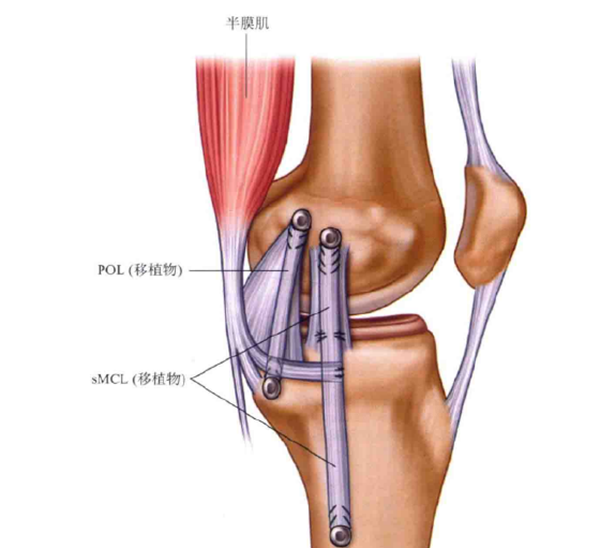

图6 解剖重建

双束重建理论上更接近于结构重建,但双束重建确定等长点存在着一定难度,手术时,分别在膝关节屈曲30°内翻条件下拉紧 MCL移植物,在伸直位0°时拉紧POL移植物,挤压螺钉固定。